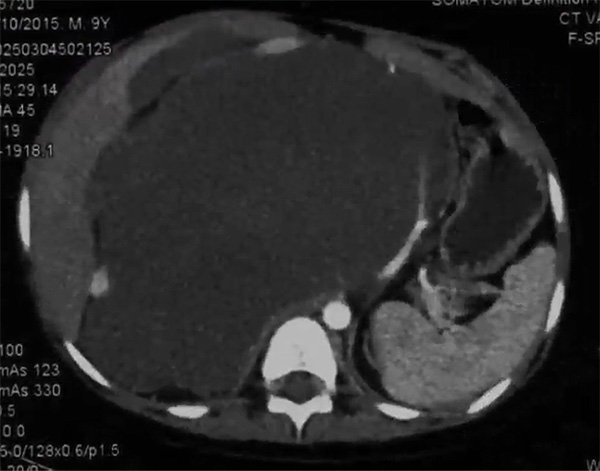

术前腹部增强CT提示腹膜后巨大肿瘤,严重侵犯周围血管及组织器官

近日,国家儿童医学中心北京儿童医院成功救治一名极其复杂的巨大腹膜后节细胞性神经母细胞瘤患儿,其肿瘤最大直径约30厘米,严重包裹重要血管、侵犯组织器官。该患儿经历了4次手术,因胆漏、胰漏、腹腔大血管破裂、腹腔感染,生命几度垂危,最终在肿瘤外科、重症医学科、麻醉科、普外科、超声科、影像中心、消化科、临床营养科、康复科、病理科、神经内科、护理部,以及北京儿童医院保定医院(以下简称保定医院)、北京医院血管外科等10余个团队紧密协作联合救治下,打赢了63天的生命“保卫战”。6月16日,患儿术后出院半个多月,恢复良好。

3月27日,王焕民主刀,带领团队在保定医院为鑫鑫手术。打开孩子的腹腔,在场的医护人员都大吃一惊:肿瘤大小约30*20*10厘米,几乎所有的腹膜后重要血管都像钢筋水泥般被巨大肿瘤包裹,血管被拉长、推挤移位,变得十分纤细,血管壁也被肿瘤侵蚀。这意味着一不小心,就很可能损伤血管,导致大出血;而且孩子的胆道、胰腺、肠系膜等重要组织结构也都被肿瘤侵犯,术后并发症风险极高。王焕民意识到,孩子的救治必将是一场艰难的持久战。经过整整11个小时的战斗,最终顺利将肿瘤切除。